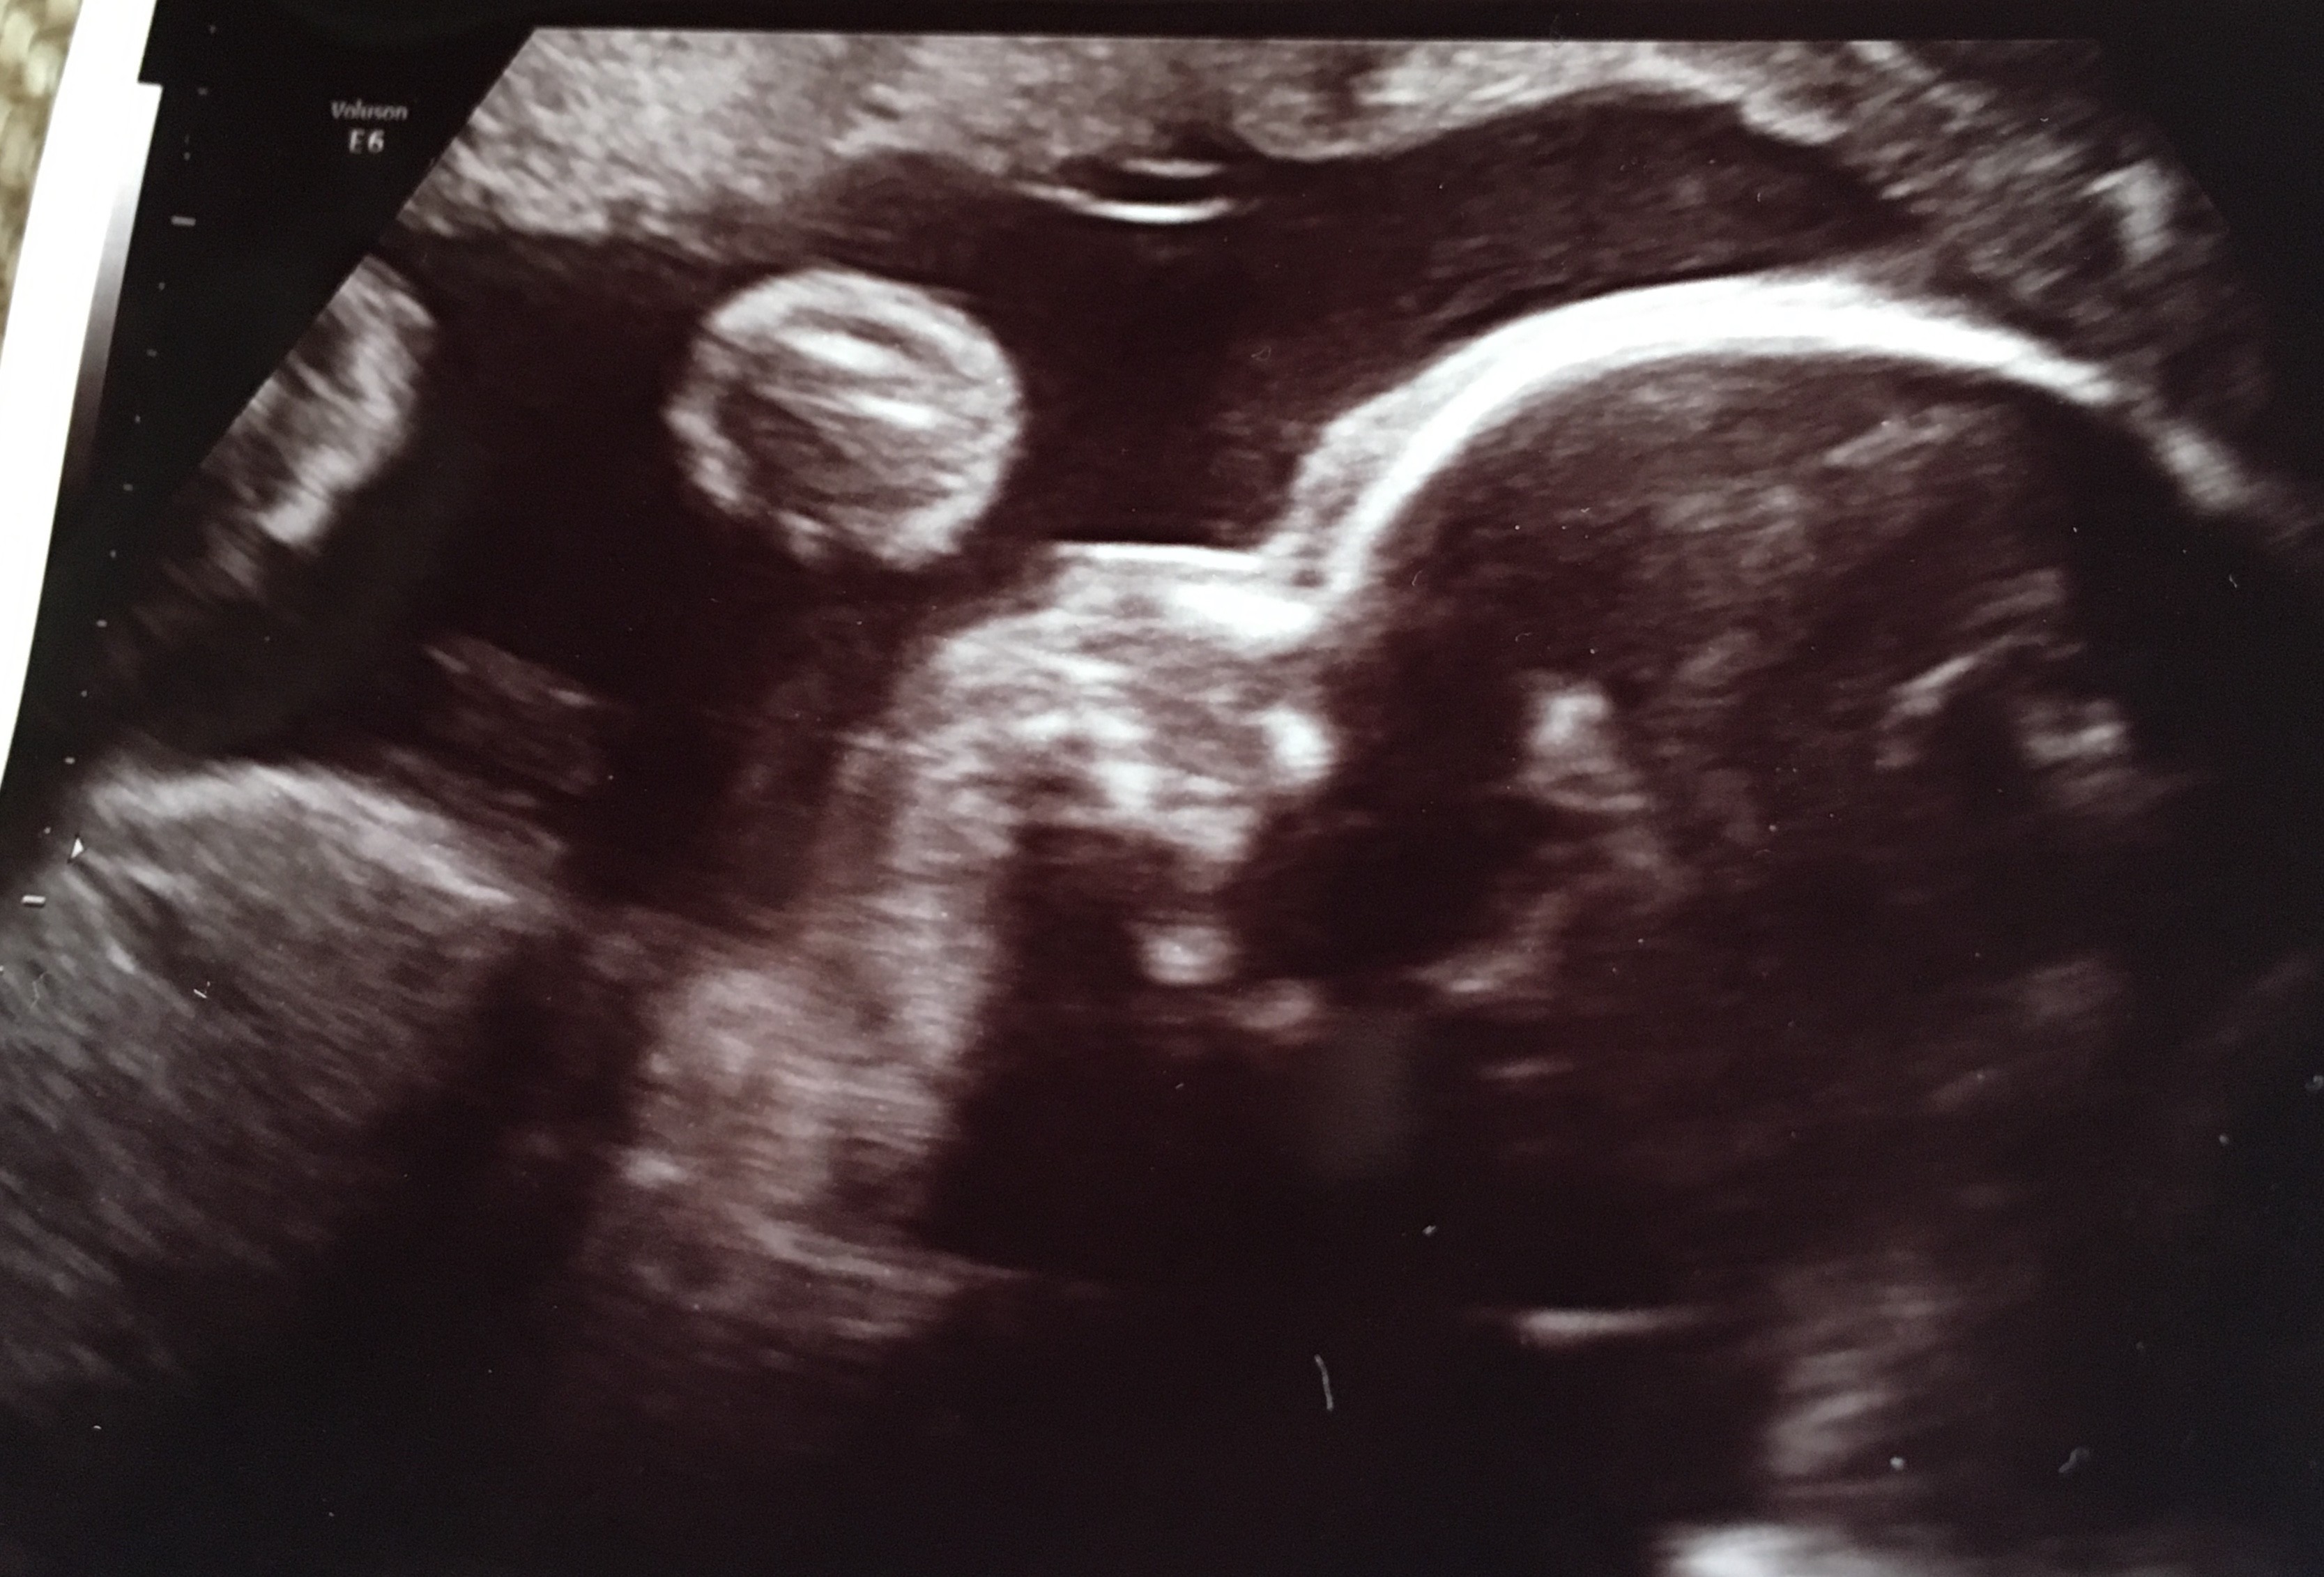

Hhaaa mam fotę, mogę w końcu z wami się podzielić twarzyczka , dziasiaj zaczynamy 27tydz Ala wazy równo kilogram, połówkowe mamy na 18 czerwca zaplanowane -o dziwo 30zl więcej niż normalna wizyta :)Zobacz załącznik 861321